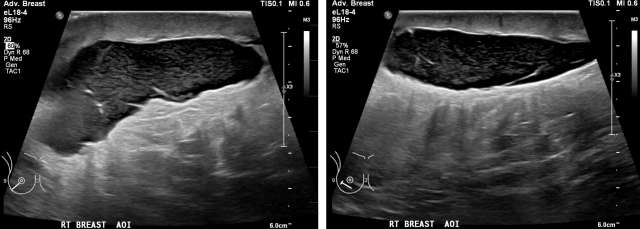

• US: Heterogenous fluid collection with fluid-fluid level, Figure 2.

Case: Post-Surgical Fluid Collections Figure 2

Figure 2 - Ultrasound demonstrating post-surgical hematoma of the right breast. Heterogenous fluid collection with fluid-fluid level (yellow arrow). There was ecchymosis overlying the area of interest in the upper inner quadrant.